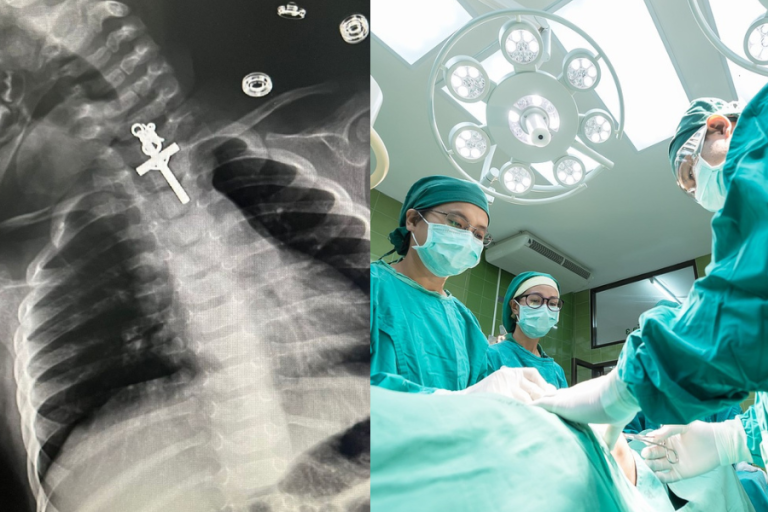

Médicos sacaron un crucifijo del esófago de una lactante: “Dios nos ha dado una oportunidad de vida

Médicos sacaron un crucifijo del esófago de una lactante: “Dios nos ha dado una oportunidad de vida"